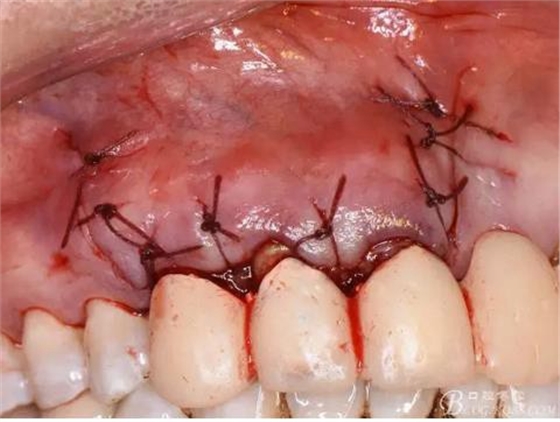

圖19.縫合